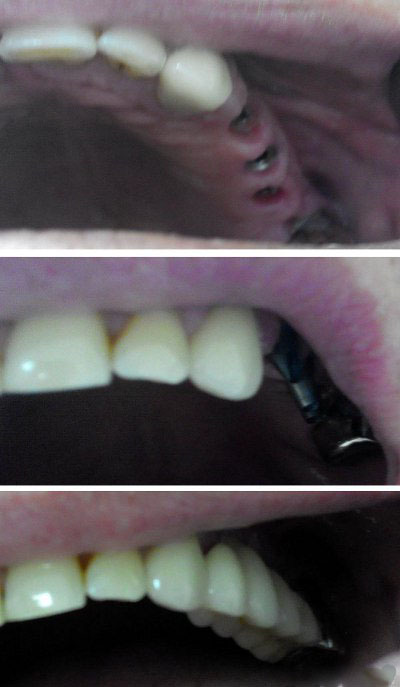

Экспресс-имплантация зубов: фото до и после

3. Установка на абатмент предварительно изготовленного временного протеза из легкой металлопластмассы.

4. Постоянное протезирование металлокерамическими или цельнокерамическими коронками.

Одномоментная классическая имплантация зубов

Эта разновидность одномоментной имплантации зубов предусматривает внедрение титанового штифта в лунку после удаления зуба, но абатмент и постоянная коронка ставятся не сразу, а через несколько месяцев после операции. На период реабилитации на имплант устанавливается временный протез, замену которого производят только после полного приживления искусственной конструкции.

Очень важна эстетика: качественно восстановленный зуб не выделяется в ряду, также недопустимо, чтобы сквозь десну были видны части импланта.